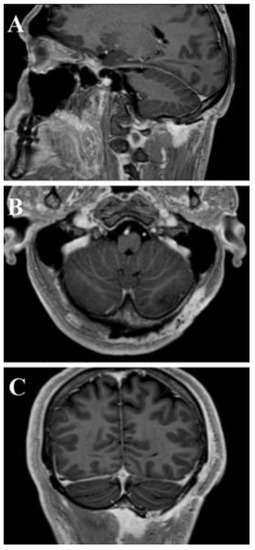

| Umana et al., 2021 | 1 | 45M | Occipital scalp | Psammomatous meningioma | Surgical resection | No recurrence at 6 months | Complete recovery |